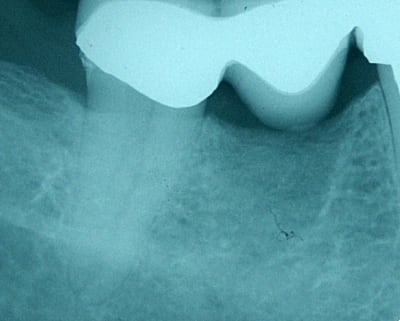

Ben voilà, j'ai fait l'endo aujourd'hui: digue, protaper, mac spadden, loupes orascoptic.

Je n'ai finalement trouvé qu'un seul gros canal dans cette fichue 47. J'ai du préparer à 45, tellement le foramen était gros. Il faisait bugger le root ZX.

Ci-jiont je vous file les radios.

La patiente est en or et a été super patiente pendant le soin.

t'as quand même eu du pot dans ton malheur,de n'avoir qu'un si gros canal,en tout cas bravo!